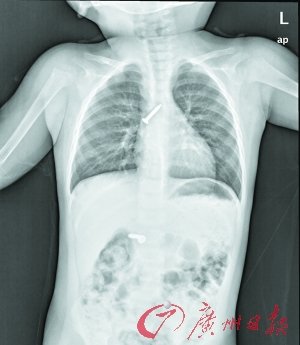

卡在女孩气管内的钢钉

“当时捏开花花的嘴,但已看不到钢钉了。料想钉子已经掉进肚子,会划破内脏……”女童的爷爷说,他赶紧带着花花到高州市人民医院胸外科就医。X光片检查显示,两枚钢钉竟然卡在了气管和小肠里。